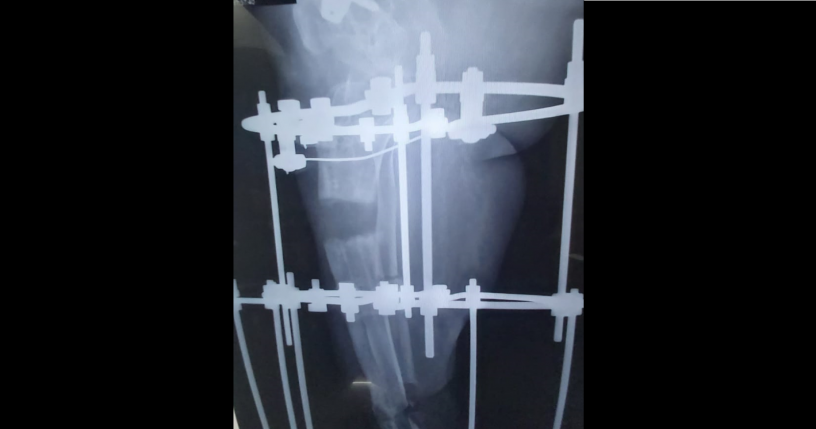

I want to point out that I did an illizarove surgery which is a ring shaped fixator which normally helps in lengthening of my right limb which was shortened by 7cm and which got deformed (equinus and dootdrop), which normally would have allowed me to walk back even with the help of a crutch.

In March, a hole appeared with pus discharge at a pin site which test result's was pseudomonas aaruginosa, with my bone growing in a curve direction, and in April the situation worsened with more acute pain and an additional bacteria (staph haemolyticus). All these 3 conditions represented a real danger of losing the limb or even death through a heart attack which normally happens due to these 2 bacterias present in my leg.